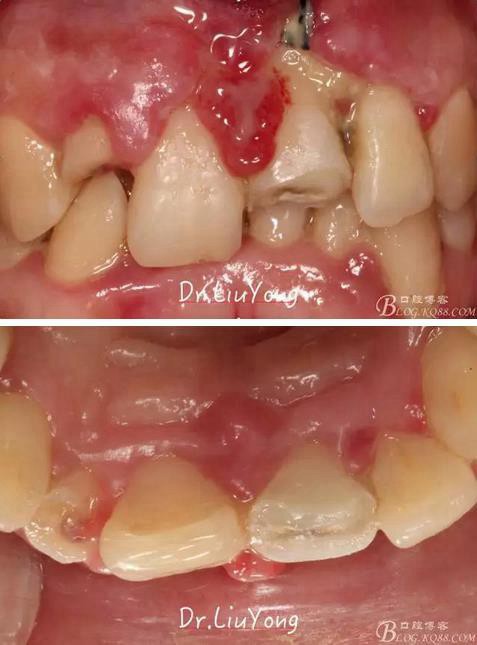

術(shù)前口內(nèi)照片如下:

骨塊固定兩周后復(fù)查,如上圖